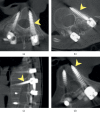

Methods: A workflow was developed to assist spinal deformity surgery using 3D printing technology. The trajectory and profile of pedicle screws were determined on the image system by the surgical team. The engineering team designed drill templates based on the bony surface anatomy and the trajectory of pedicle screws. Their effectiveness and safety were evaluated during a preoperative simulation surgery. The surgery consisted in making a pilot hole through the drill template on a computed tomography- (CT-) based, full-scale 3D spine model for every planned segment. Somatosensory evoke potential (SSEP) and motor evoke potential (MEP) were used for intraoperative neurophysiological monitoring. Postoperative CT was obtained 6 months after the correction surgery to confirm the screw accuracy.

Results: From July 2015 to November 2016, we performed 10 spinal deformity surgeries with 3D printing technology assistance. In total, 173 pedicle screws were implanted using drill templates. No notable change in SSEP and MEP or neurologic deficit was noted. Based on postoperative CT scans, the acceptable rate was 97.1% (168/173). We recorded twelve pedicle screws with medial breach, six with lateral breach, and five with inferior breach. Medial breach (12/23) was the main type of penetration. Lateral breach occurred mostly in the concave side (5/6). Most penetrations occurred above the T8 level (69.6%, 16/23).